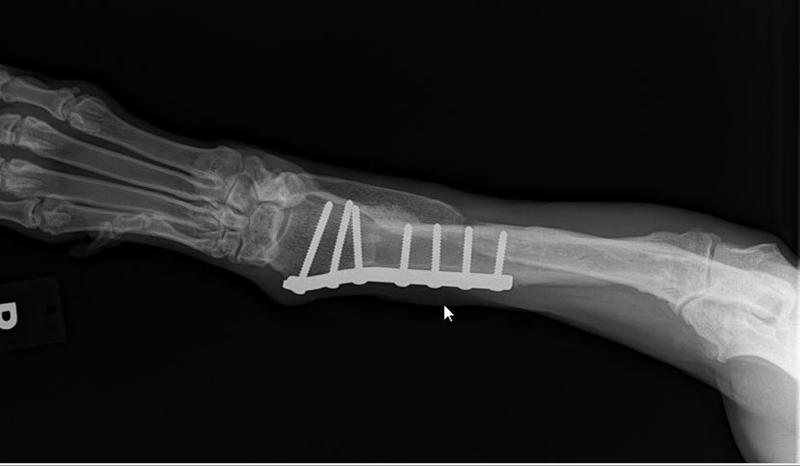

Her radius curvus syndrome was addressed, a bloat survivor and nothing ever held her back!